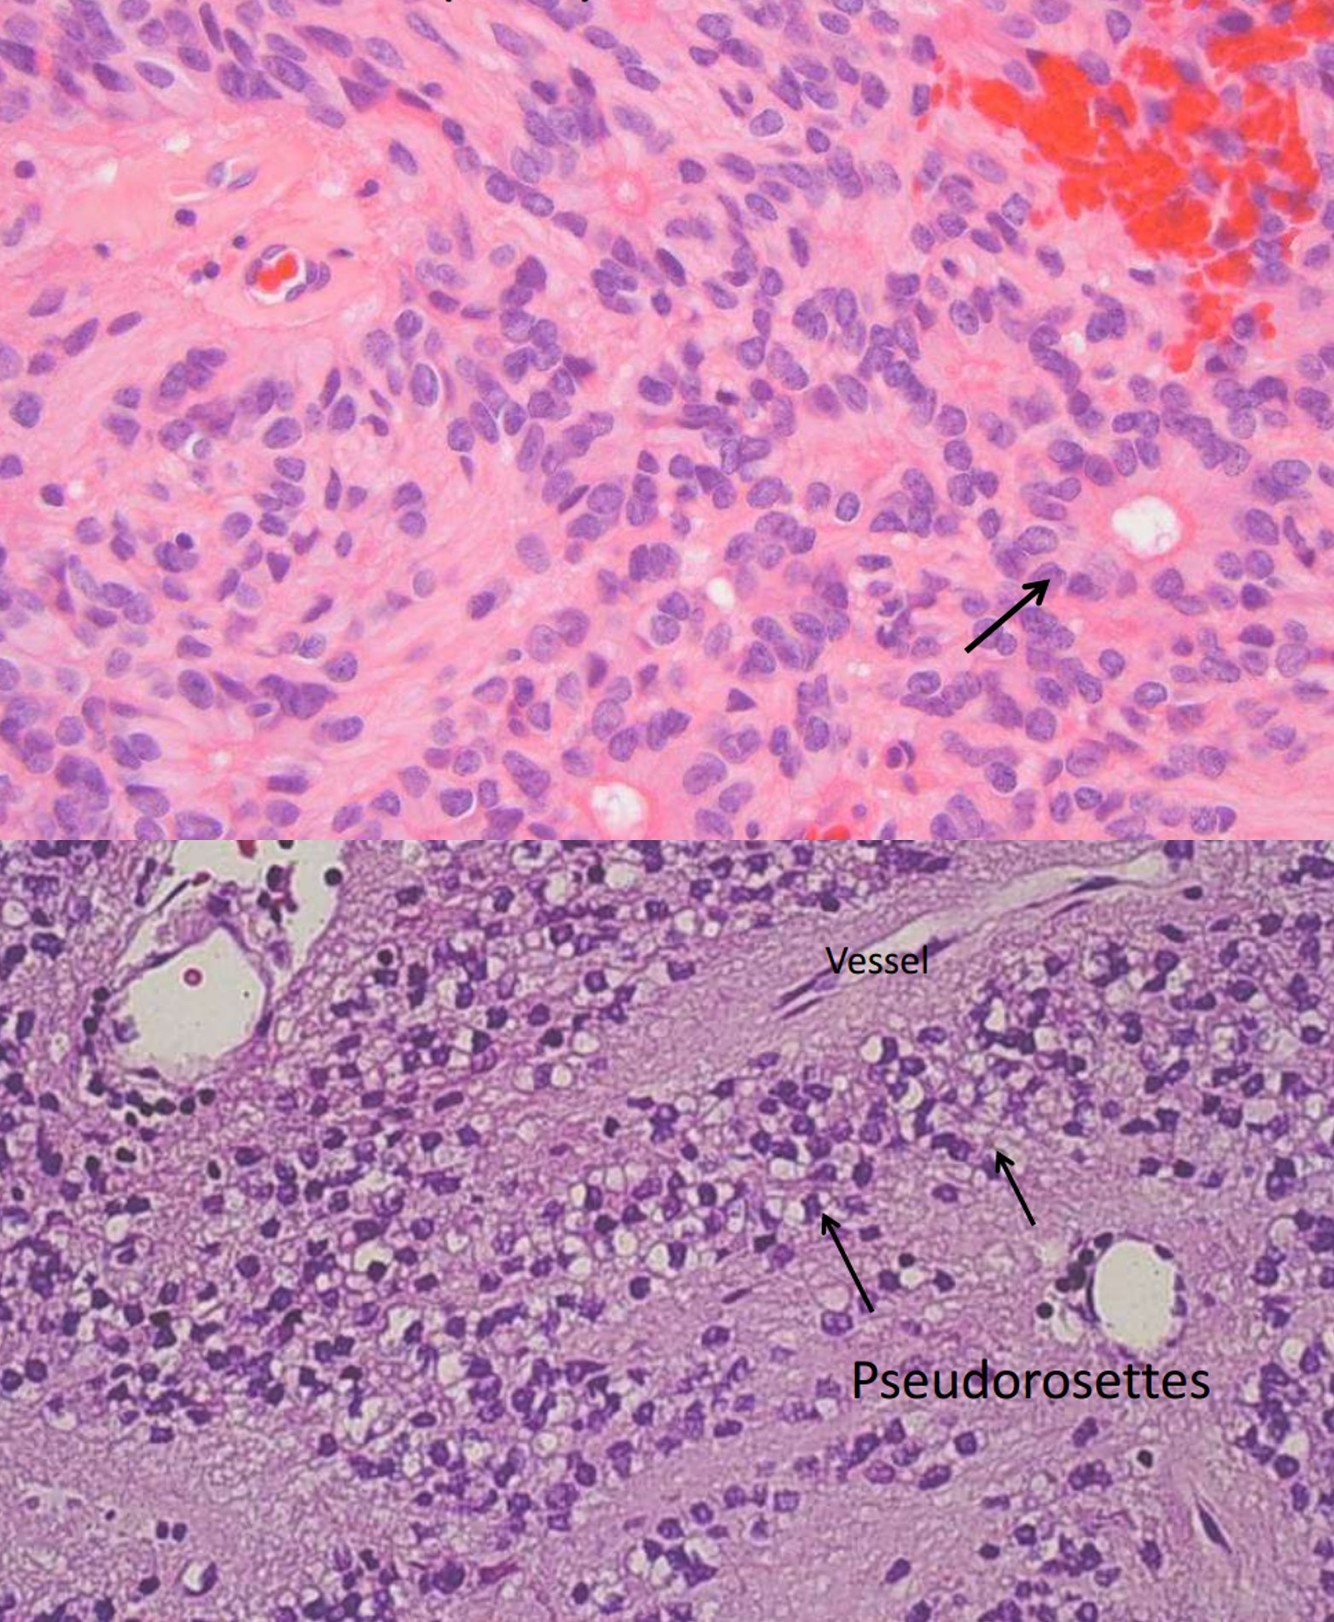

Ganglioglioma, GI